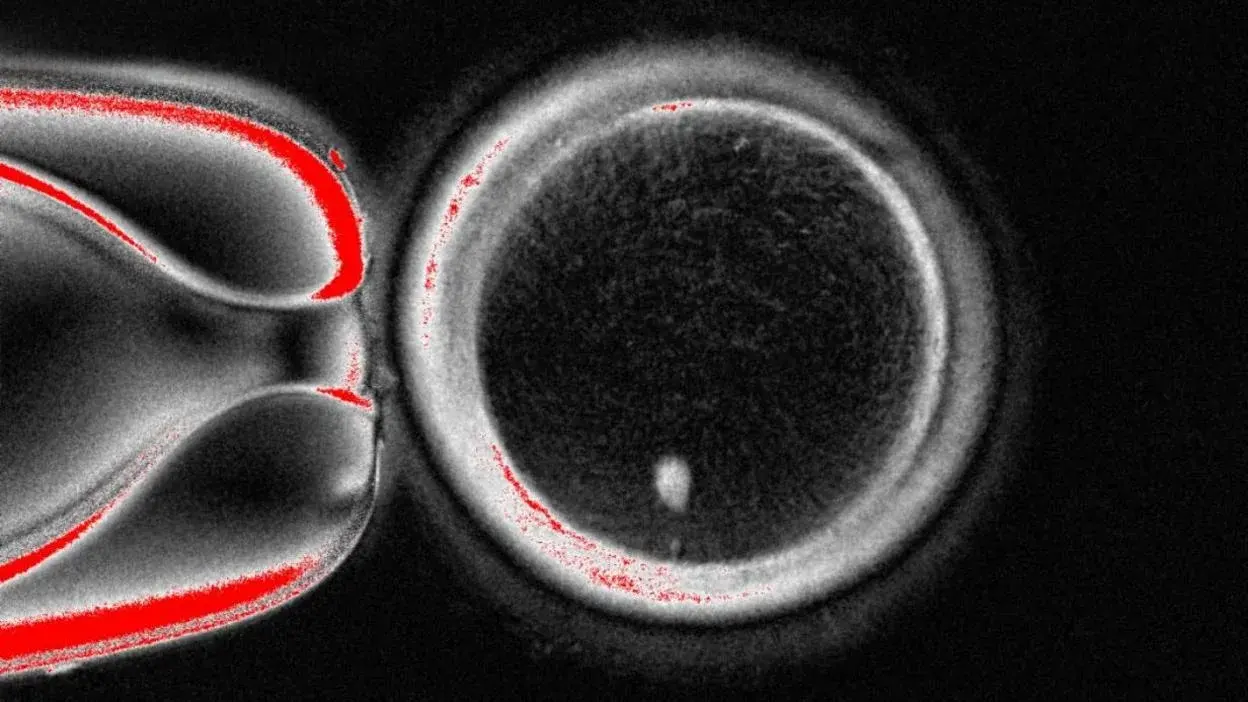

นักวิทย์สร้างตัวอ่อนมนุษย์ จาก DNA ผิวหนังได้แล้ว!!

นักวิทยาศาสตร์ในอเมริกา ได้สร้างความฮือฮาในวงการวิทยาศาสตร์ ด้วยการสร้างตัวอ่อนระยะเริ่มต้นของมนุษย์จาก DNA ในเซลล์ผิวหนังได้เป็นครั้งแรกของโลก!! ซึ่งการค้นพบนี้ถือเป็นความหวังใหม่สำหรับผู้ที่มีบุตรยาก รวมถึงคู่รักเพศเดียวกัน ที่อาจมีบุตรด้วยการสืบทอดทางพันธุกรรมร่วมกัน ซึ่งจะมีผลตามกฎหมายนั่นเอง...

โดยทีมวิจัยจากมหาวิทยาลัยสุขภาพและวิทยาศาสตร์ออริกอน ในอเมริกา ซึ่งนำโดยศาสตราจารย์ "ชูครัต มิตาลิปอฟ" ได้ใช้เทคนิคเดียวกับการสร้าง "แกะดอลลี่" โดยการนำนิวเคลียสจากเซลล์ผิวหนัง ซึ่งบรรจุรหัสพันธุกรรมทั้งหมด มาใส่ในไข่ของผู้บริจาคที่ถูกถอดข้อมูลทางพันธุกรรมออกไปแล้ว จากนั้นกระตุ้นให้เกิดการแบ่งตัว จนเป็นไข่ที่สมบูรณ์ แล้วนำไปผสมกับสเปิร์ม ผลการศึกษาดังกล่าว ถูกตีพิมพ์ในวารสารทางการแพทย์ "การสื่อสารธรรมชาติ" พบว่า "ไข่ 82 ใบที่ถูกผสมกับสเปิร์ม สามารถพัฒนาเป็นตัวอ่อนระยะเริ่มต้น ที่เติบโตได้นานถึง 6 วัน" ถึงแม้ว่าจะยังไม่มีไข่ใบใดพัฒนาไปได้เกินกว่านี้ แต่ "ชูครัต มิตาลิปอฟ" ได้กล่าวถึงความสำเร็จนี้ว่า "เราทำบางอย่างที่เคยคิดว่า "เป็นไปไม่ได้" สำเร็จแล้ว!!"

ถึงแม้จะเป็นความก้าวหน้าครั้งสำคัญ แต่ผู้เชี่ยวชาญด้านเวชศาสตร์การเจริญพันธุ์ ก็ชี้ให้เห็นว่า "ยังจำเป็นต้องมีการอภิปรายอย่างเปิดกว้าง ต่อสาธารณชนเกี่ยวกับความเป็นไปได้ และ ความเป็นจริงทางวิทยาศาสตร์" และ "แน่นอนว่าจะตามมาด้วยข้อกังวล ด้านความปลอดภัยที่สำคัญ..." "ชูครัต มิตาลิปอฟ" ยอมรับว่า "เทคนิคนี้ยังไม่สมบูรณ์ เนื่องจากในการทดลองนี้ ไข่ได้สุ่มเลือกทิ้งโครโมโซม ทำให้เกิดความผิดปกติ เช่น มีโครโมโซมซ้ำชนิดกัน 2 ชุด หรือบางชนิดก็ไม่เหลืออยู่เลย ซึ่งตามหลักแล้วไข่จะต้องมีโครโมโซมชนิดละ 1 ชุด จากทั้งหมด 23 ชนิด เพื่อป้องกันโรคหรือความผิดปกติ" นอกจากนี้ "อัตราความสำเร็จยังคงต่ำอยู่ที่ประมาณ 9 เปอร์เซ็นต์ และ โครโมโซมยังขาดกระบวนการจัดเรียงดีเอ็นเอใหม่ที่สำคัญที่เรียกว่า "กระบวนการไขว้เปลี่ยนของโครโมโซม" ตอนนี้ วิธีการนี้ยังอยู่ในระดับของการค้นพบทางวิทยาศาสตร์ และ จำเป็นต้องได้รับการพัฒนาปรับปรุงอย่างมีนัยสำคัญ ซึ่งอาจต้องใช้เวลาประมาณ 10 ปี ก่อนที่จะถูกพิจารณานำมาใช้จริงในทางคลินิก"

อย่างไรก็ตาม เป้าหมายสูงสุดของการพัฒนาเทคโนโลยีนี้ คือ การช่วยเหลือผู้มีภาวะมีบุตรยาก เช่น หญิงสูงอายุที่ไม่มีไข่เหลืออยู่ ชายที่ไม่สามารถผลิตอสุจิได้เพียงพอ หรือ ผู้ที่ผ่านการรักษาโรคจนทำให้มีบุตรยาก อีกทั้งยังเปิดโอกาสให้คู่รักเพศเดียวกัน สามารถมีลูกที่มีพันธุกรรมเชื่อมโยงกับทั้งคู่ได้ ซึ่ง "ชูครัต มิตาลิปอฟ" กล่าวยืนยันความตั้งใจนี้ว่า "ในอนาคตมันจะต้องเป็นแบบนั้น เพราะผู้ที่ไม่สามารถมีบุตรได้ มีจำนวนมากขึ้นเรื่อยๆ ซึ่งตอนนี้เราก็เห็นแล้วหนิว่า อัตราการเกิดในโลกนี้ต่ำเตี้ยเรี่ยดิน..."